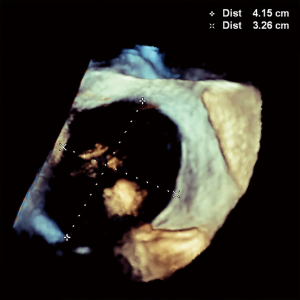

A 64-year-old female with no previous cardiac history progressively developed exertional pre-syncope and decreased endurance. Work-up revealed a dilated right ventricle and 3D-TEE illustrated a 21×13 mm secundum ASD (Figure 1). A 20 mm Amplatzer™ Septal Occluder (ASO) was selected for closure based on 3D-TEE sizing. During the procedure, RT3D-TEE aided in directly visualizing parallel apposition of the deployed left atrial ASO disk to the left atrial septum. After the right atrial disk was deployed, color Doppler imaging ensured appropriate device seal. Both left and right atrial disks were clearly identified with 3D right atrium and left atrium en face views confirming circumferential capture of the rim tissue (Figure 2). Adequate room posteriorly was ensured with 3D-TEE and helped show stability post-release with no evidence of encroachment into the aorta anteriorly.